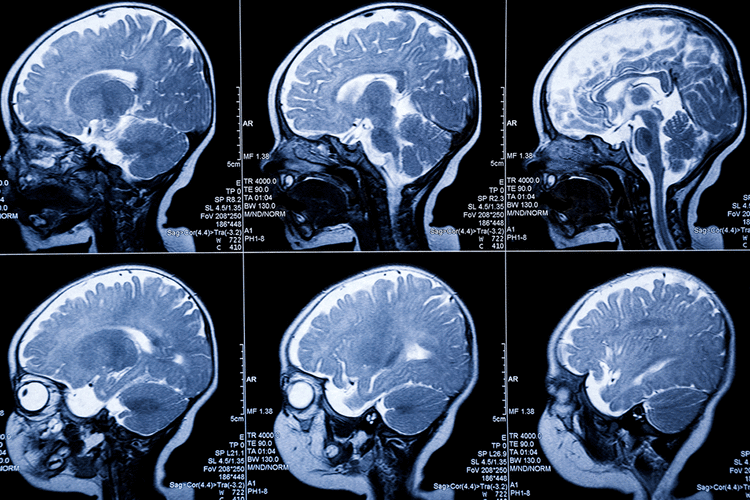

- Ancak teşhis ve tedavilere karşın genç adamın durumu kötüleşmeye devam etti ve sık sık nöbet geçirme ve göz kararması çekmeye başladı. Tümörün niteliği ve neden geliştiğini araştırmaya başlayan doktorlar şoke edici bir gerçekle karşılaştılar. Whag Lei’nin beyninde 12 santimetre uzunluğunda bir tenya yaşıyordu. 2018 yılında, doktorlar Lei’nin beyninde tenya yaşadığını keşfetti ve hastaya parazitin işlem yapmasının riskli bir bölgede olduğu düşünüldüğü için cerrahi olmayan bir tedaviye başlaması önerildi. Ancak ilaçlı tedavi işe yaramayınca ameliyat kaçınılmaz oldu.

- Guangdong Sanjiu Beyin Hastanesi’nde 2 saatlik ameliyatın ardından, sağlık görevlileri raporlara göre, kedilerin ve köpeklerin bağırsaklarında yaygın olarak bulunan fakat nadiren insanlarda görünen Sparganum mansoni paraziti çıkardılar. Ameliyatı yapan doktorlar, “Canlı tenya beyinde hareket ediyordu ve hepsini çıkarmak zorunda kaldık, aksi halde kalan kısım tekrar büyüyebilirdi” açıklaması yaptı. Parazitlerden nasıl korunmak gerekir? İnsanlar, iyice pişirilmesi gereken kurbağaları, salyangozları ve yılanları pişirirken dikkatli olmalıdırlar. Ayrıca, kaynatılmadıkça doğal ortamlardan su içmeyin.(Posta)